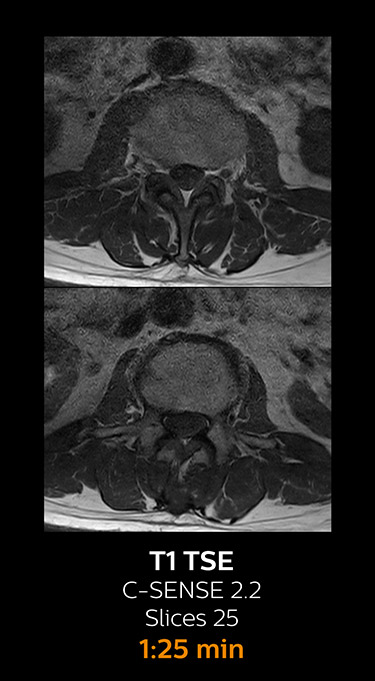

which corresponds to 34% reduction.

With Compressed SENSE, the scan time for the routine lumbar spine examination at KNC was reduced from 11:41 to 8:17 minutes,

MRI examination of the lumbar spine with Compressed SENSE

Ingenia 3.0T CX

Scan time 8:17 min. (was 11:41 min. without Compressed SENSE)